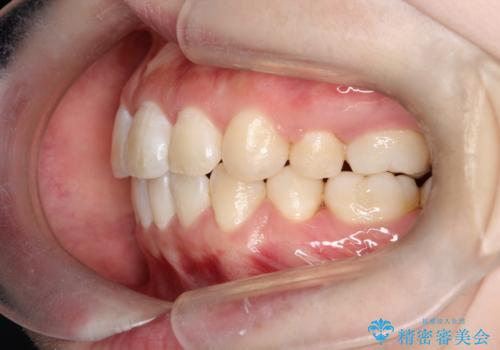

- 20代女性

- 矯正装置

- 審美装置

- ”口元を下げたい”が主訴で来院されました。

抜歯してワイヤー矯正を行い、口元も改善され大変満足していただきました。

小臼歯の抜歯を行うことで口元を改善することができました。